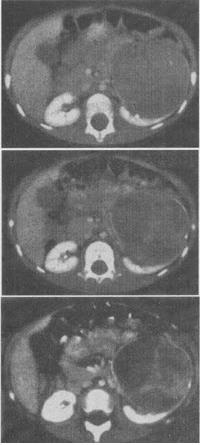

- 单项选择题1、 女,54岁,发现腹部包块,根据所示图像,最可能的诊断是()。

A、左侧肾癌

B、左侧单纯性肾囊肿

C、左侧肾囊肿合并出血

D、左侧囊性肾癌

E、左侧肾血管平滑肌脂肪瘤